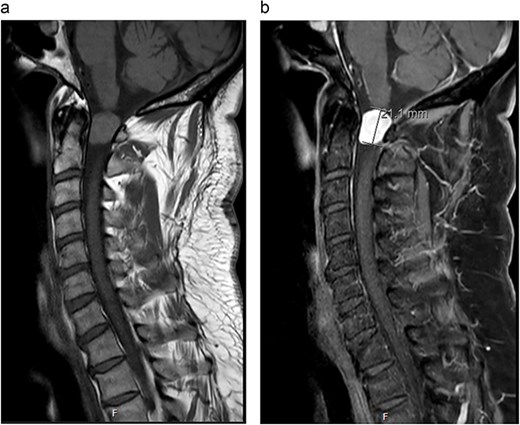

MRI cervical spine (Fig. 1) demonstrated an extramedullary intradural lesion at C1/2 within the right aspect of the canal distorting and compressing the cord to the left with associated cord signal changes. The lesion is isointense on T1- and T2-weighted images and measures ~1.7 × 2.0 × 2.1 cm. Following contrast (Fig. 2), there is homogenous enhancement of the lesion. Computed tomography of thorax, abdomen, and pelvis showed no evidence of primary lesions or skeletal deposits.

(a) Pre-operative axial MRI cervical spine T1-weighted image without contrast (across the C1 level). (b) Pre-operative axial MRI cervical spine T1-weighted image with contrast (across the C1 level).